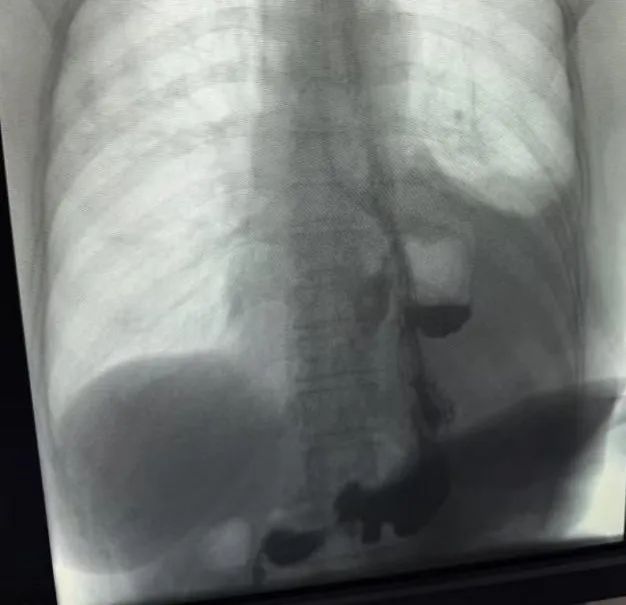

七旬大爷餐后日常散步,却发生「九死一生」的急重症!这种凶险的疾病,竟然是平时不起眼的「小毛病」所引起的...... 凌晨 4 点,大家都在安睡,71 岁的刘大爷(化名)却躺在山一大二附院急诊内科抢救室的病床上痛苦不已,原来他在饭后散步后,突发上腹部疼痛、恶心伴呕吐,体温也在逐渐升高至近 38°C。急诊医生忙而不乱,逐一排查老人心脏及大血管问题,回报结果显示正常。进一步完善上腹部平扫加强化 CT,检查单上赫然写着刘大爷的部分胃腔经食管裂孔疝入胸腔,膈上胃腔扩张、内见多量气液平面,导致刘大爷腹痛的原因被揪了出来!

「立马联系胸外科急会诊!」急诊医生马上拨通了胸外科的值班电话,不到 10 分钟夜班大夫迅速到位,仔细为刘大爷查体并阅读 CT 影像,考虑到刘大爷多年便秘病史并与影像科大夫进一步核对后,判断刘大爷并不是食管裂孔疝,而是更为凶险的急重症——食管破裂!时间就是生命!一场凌晨的抢救拉开序幕!

(急诊入院时胸部 CT,可见纵隔积气)

夜班医生第一时间与家属介绍患者情况,紧急入院,迅速转运至胸外科病房,到达病房立即为患者建立静脉通道、输液、下胃管。刘大爷腹痛症状明显好转,病情危急,须立即手术!手术室团队迅速做好了术前准备。考虑到刘大爷既往因小肠疾病先后做过两次手术,腹腔粘连可能较重并排查腹腔脏器有无损伤及污染,在确定腹腔内无明显器官损伤以及胃内容物后,张强主任和纪波主任当机立断,立刻左侧开胸修补食管裂孔。